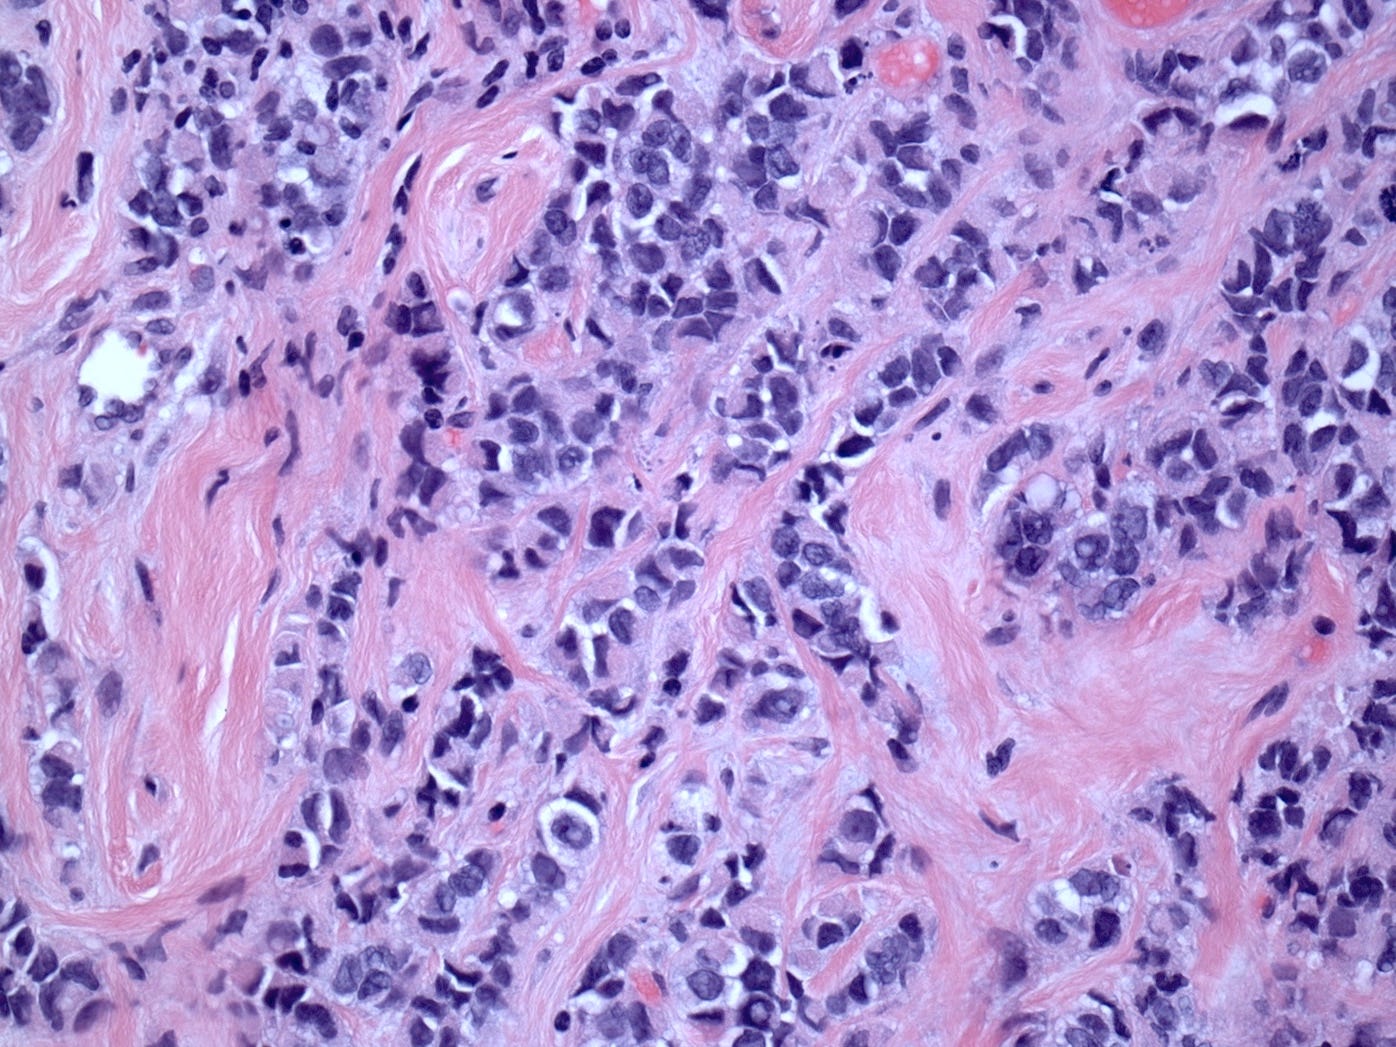

Pleomorphic lobular carcinoma is a less common subtype of infiltrating lobular carcinoma (15%) with cellular dyscohesion and histologic architecture similar to classic infiltrating lobular carcinoma plus pleomorphic cytologic features similar to those seen in pleomorphic LCIS or high grade DCIS. Its molecular profile and immunostaining pattern (including the loss of E-cadherin) support a common origin with infiltrating lobular carcinoma with the acquisition of further molecular alterations.

Most patients present with a poorly defined palpable breast mass. Patients typically have a more advanced stage (large tumors and axillary lymph node metastasis) than patients with invasive ductal carcinoma (IDC). The cancer is more frequently multifocal or multicentric.

Its prognosis is similar to that of other high grade breast carcinomas of similar stage or grade, although some studies suggest its histology is associated with poorer survival.

Pleomorphic lobular carcinoma - microscopic images

The precursors of pleomorphic lobular carcinoma are pleomorphic lobular carcinoma in situ and classic LCIS, which frequently coexist. They were discussed previously.